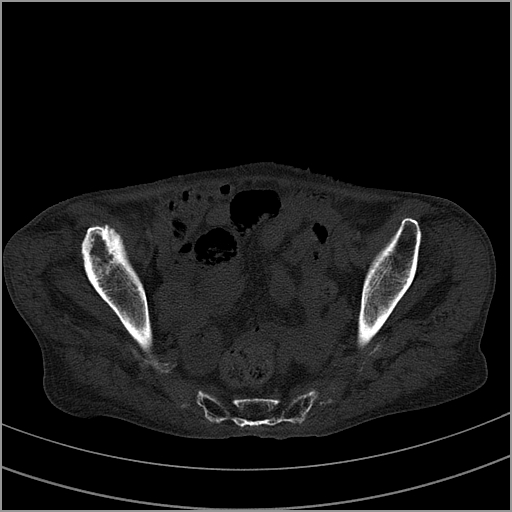

以下是引用老爱克斯新网客在2009-2-3 19:42:00的发言:[br]右侧髋臼及右侧股骨头可见明显骨质破坏,以溶骨性破坏为主,无明显硬化,髋关节间隙变窄,周围软组织明显肿胀,密度不均,脂肪间隙消失。[br] 诊断:右侧髋关节感染性病变,右侧髋关节结核的可能大。[br] 鉴别诊断:1.股骨头缺血坏死,单纯股骨头缺血坏死病例不会累积髋臼骨破坏。2。退行性关节炎,以骨质增生为主,伴有关节面硬化,骨质破坏呈多发小囊状破坏为主,其周围可见硬化环。3.股骨头缺血坏死晚期(第四期)骨质破坏可伴髋关节退行性变,可有骨质增生,但此时骨破坏以股骨头破坏为主,不应该伴有髋臼骨质破坏,因为股骨头的骨破坏是因血运中断,而没有髋臼的血运中断,又没有细菌的感染,怎么能造成髋臼的骨破坏呢。